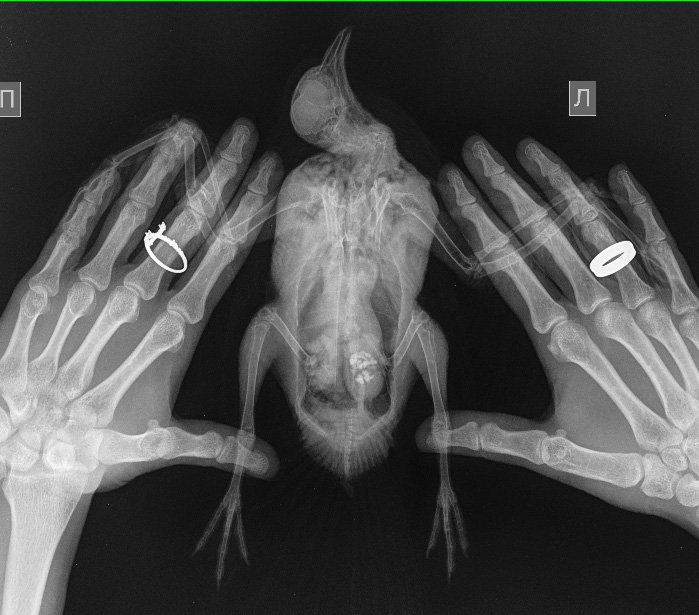

Zosia Опубликовано 29 июля, 2021 #15 Опубликовано 29 июля, 2021 Вам надо сделать еще раз снимок, с аккуратно и полностью раскрытым поврежденным крылом. Фиксировать к основанию (над кассетой) бумажным скотчем, придерживать крыло у плеча. Потому что на вашем первом снимке- полный многооскольчатый перелом локтевой кости с малым смещением, а вот лучевая кость выглядить выбитой (оторванной), что озанчает внутрисуставный перелом...Но т.к. крыло снято не в раскрытом состоянии- степень повреждения оценить трудно. Что там с легкими- а что-то есть- так же плохо видно. С успехом это м.б. микоплазмоз, или клебсиелльная пневмония, или тупо аллергическая реакция на что-то. Глубокий мазок из глотки и помет- и красить по Циль-Нильсену. Смотреть КУМ и криптоспоридии. Ну и банальный общий анализ помета (копрограмма) Пока основная терапия- снятие боли (НПВС), травматин, миорелаксант можно (толперизон). Фиксация - магкая, в сетчатый трубчатый бинт, со свободным здоровым крылом. Вот аткого типа: https://public.fotki.com/Shemlik/bae5/b70c.html https://public.fotki.com/Shemlik/bae5/2.html#media https://public.fotki.com/Shemlik/bae5/3.html#media

Cara Mia Опубликовано 4 августа, 2021 Автор #17 Опубликовано 4 августа, 2021 Добрый день! Снимки нового рентгена голубя были сделаны в клинике "Главное Хвост". Лечащий врач этой клинике после осмотра и на основании этих снимков сделала такую выписку (фото) с диагнозом (диф.) Аэросаккулит, (диф.) Аэроцистит. По перелому сказала, что оба крыла работают, оно начинает срастаться, но необходимо извлечь остатки раздробленной кости, для чего нужна операция, а вывихи вправлять в Беларуси не могут. Посоветовала записаться на прием к главному врачу-орнитологу клиники А. Полозу, который до 14.08. находится в отпуске. Назначены следующие препараты: 1. Амоксициллин 250 мг - внутрь по 1/16 содержимого капсулы 1 раз в день, на протяжении 10 дней. 2. Мелоксидил сусп. - внутрь по 0,1 мл 1 раз в день, на протяжении 10 дней. 3. Нистатин 500000 ед. - внутрь по 1\6 таблетке 2 раза в день, на протяжении 14 дней. 4. Карсил - внутрь по 1/10 таблетки 1 раз в день на протяжении 14 дней. Не входит ли это в противоречие с уже существующим назначением другого врача?: 1. Ципрофлоксацин, 250 мг, внутрь по 1/10 таблетки 2 раза в день 3 недели (ПРОДОЛЖЕН С 14 ДО 21 ДНЯ ПОСЛЕ ПЕРВЫХ СНИМКОВ РЕНТГЕНА) Курс начат 22.07 Курс будет закончен 12.08 2. Мелоксикам 7.5 мг, внутрь по 1/10 таблетки 1-2 раз в день, 7 дней, далее по состоянию Курс начат 20.07 Курс закончен 27.07 3. Метронидазол 250 мг внутрь по 1/8 таблетки 1 раз в день 5-7 дней Курс начат 20.07 Курс закончен 26.07 4. Нистатин 500000 ед. внутрь по 1/4 таблетки 2 раза в день в течение месяца (ДОБАВЛЕН ПОСЛЕ ПЕРВЫХ СНИМКОВ РЕНТГЕНА) Курс начат 22.07 Курс будет закончен 22.08 5. Празицид, суспензия для котят внутрь по 0.3 мл 2 раза с интервалом 14 дней Курс начат 23.07 Курс будет закончен 07.08 6. Стронгхолд 1/2 пипетки 2 раза с интервалом 21 день Курс начат 18.07 Курс будет закончен 07.08 СОСТОЯНИЕ: Голубь стал беспокойным, постоянно пытается выбраться из контейнера, часто машет крыльями. Ест хорошо, по назначению врача (каши, семена подсолнечника, льна), морковь и салат добавляю,но он не ест почти). Несколько дней назад цвет стула изменился на зеленый (фото), врач связала это с большим количеством медпрепаратов. Во время кормления лекарствами через пипетку сейчас вертит головой, оказывает сопротивление (раньше такого не было). Также при приближении руки убегает, вырывается и немного "кряхтит" (так, как это делают утки). Звук могу скинуть, если нужно. На приложенных гифках он сегодня после приема у врача, в состоянии стресса. Также Ахова птушак Бацькаўшчыны (@apb_birdlife_belarus посоветовала мне связаться с Зоей Кенько. Спасибо ей большое, что она сразу же ответила, и помогла с расшифровкой назначений, а также с контактами хороших хирургов и терапевта для проведения операции. АНАЛИЗЫ: На анализы есть возможность записаться в субботу, этого врача советуют консультант Зоя Кенько и Валерия Сороко (ВетТаргет). Стоит ли ждать продолжать курс, менять курс лечения, не дожидаясь анализов (мазок из зоба, копрограмма) до субботы хорошего врача (Вересовая Екатерина)? К сожалению, в других клиниках или не делают эти анализы, или (по отзывам волонтеров и хозяевов) делают их не совсем качественно. Прошу Вас помочь с диагностикой голубка и спасибо большое за помощь! @Zosia @OFA @маленький принц

Zosia Опубликовано 8 августа, 2021 #21 Опубликовано 8 августа, 2021 Срастаются. Будет некоторое ограниечение в функционале, но рабочее. А отломок- может и сам отторгнуться, через образовавшийся (в идеале) свищ. Остеогенон проперйте. 1/20 капсулы в сутки, три недели.